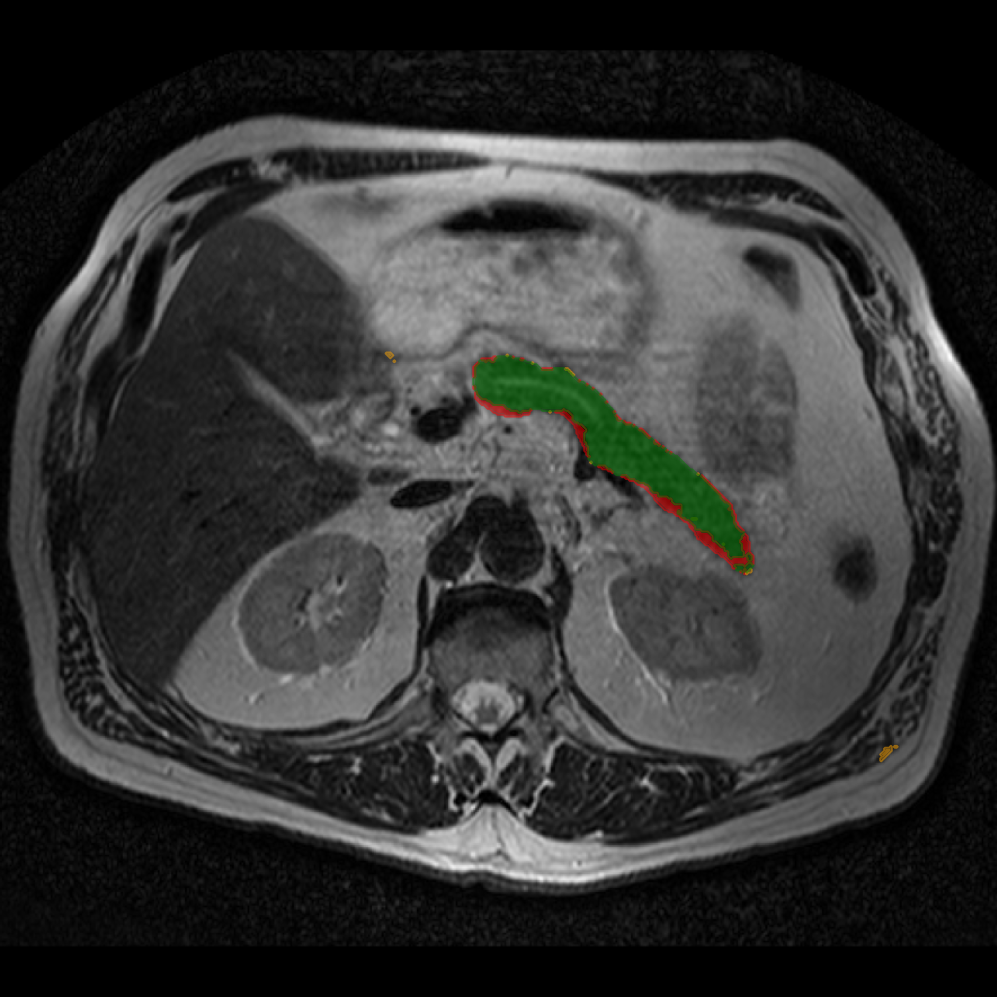

Accurate pancreas segmentation is a critical prerequisite for precise cyst analysis and classification. Recently, we developed PanSegNet [zhang2025large], a novel segmentation architecture incorporating linear self-attention layers [zhang2022dynamic] within the nnUNet framework [isensee2021nnu] to enhance global information modeling capabilities while maintaining computational efficiency (Fig. 1). PanSegNet demonstrated exceptional segmentation performance across both T1W and T2W modalities, achieving mean dice scores of 86.817.30% and 89.626.38%, respectively (Table 1, Fig. 2b-c). This performance significantly exceeded that of Swin-UNETR [hatamizadeh2021swin], one of the most used state-of-the-art transformer-based medical segmentation models, which achieved dice scores of 79.091.40% and 76.290.66% for T1W and T2W, respectively (). In this study, we integrated PanSegNet into our Cyst-X engine along with a classifier for risk prediction. In Section 2.2, we show that the choice of segmentation model affects the classification results. The performance advantage of PanSegNet was consistent across all seven medical centers, demonstrating robust generalization despite variations in imaging protocols and equipment (Table 1). This cross-institutional reliability is particularly important for clinical applications, where model performance must remain consistent regardless of imaging site or acquisition parameters.

2.2.1 Importance of accurate pancreas segmentation in classification

To assess the importance of accurate pancreas segmentation in classification, we evaluated how different ROI sources affect DenseNet-121’s performance. Specifically, we compared classification results using ROIs generated by PanSegNet and Swin-UNETR, both under centralized learning, against a baseline using radiologist-defined ROIs. As shown in Table 2, using PanSegNet’s masks resulted in only a modest performance decline, reflecting its strong segmentation quality. In contrast, Swin-UNETR led to a more substantial drop, demonstrating that inferior segmentation can directly compromise classification. For 3-class classification, the mean AUC dropped from 75.59% (radiologist ROI) to 72.26% with PanSegNet, and further to 66.95% with Swin-UNETR on T1-weighted images. On T2-weighted scans, the AUC declined from 81.09% to 74.18% (PanSegNet) and to 69.63% (Swin-UNETR). A similar trend was observed in 2-class classification: on T1W, AUC dropped from 78.13% to 74.84% (PanSegNet) and 70.20% (Swin-UNETR); on T2W, from 82.37% to 77.01% and 68.92%, respectively. These results emphasize that accurate segmentation—particularly via PanSegNet—is not only essential for volume estimation but also critical to preserving downstream classification performance in the Cyst-X pipeline.